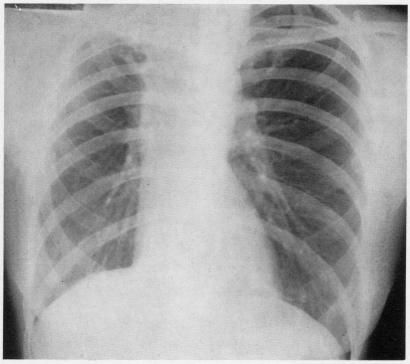

Pulmonary monosporosis is an uncommon form of fungal disease of the lung and bronchorespiratory passages. To date, only six isolated cases have been reported in the literature. It is the purpose of this communication to present the clinical findings, laboratory data, radiographic appearance, and description of the pathology findings in three additional cases identified at the Missouri State Sanatorium. The fungus is present in the soil and has a world-wide distribution. It has been shown to produce localized lesions in the foot called maduromycosis. Pulmonary infection due to this fungus has no characteristic clinical pattern, but the cultural characteristics of permit specific identification. Histologically, the pulmonary involvement shows a variegated non-specific pattern. In the majority of cases, well-defined, predisposing factors are present. A review of the reported six cases and a study of our three cases strengthens our belief that the organism acts as a secondary invader. To date, no mode of therapy has appeared to exert a beneficial influence on the course of the disease. To our knowledge, no clinical trial using any of the antifungal agents has been attempted. Surgical treatment is indicated whenever the lesions are considered resectable. From our observations, we conclude that pulmonary infection with could be recognized more frequently if physicians were more aware of this fungal infection and if the mycology laboratories would take additional care in specific identification.

肺单孢子菌病是肺部和支气管呼吸道真菌病的一种罕见形式。迄今为止,文献中仅报道了6例孤立病例。本报告旨在介绍在密苏里州疗养院发现的另外3例病例的临床发现、实验室数据、影像学表现及病理检查结果。该真菌存在于土壤中,分布于世界各地。它已被证明可在足部产生称为足分支菌病的局部病变。由这种真菌引起的肺部感染没有特征性的临床模式,但该真菌的培养特征可用于特异性鉴定。组织学上,肺部受累表现为多样化的非特异性模式。在大多数病例中,存在明确的易感因素。对已报道的6例病例的回顾以及对我们3例病例的研究强化了我们的观点,即该病原体为继发性入侵者。迄今为止,尚无治疗方式似乎对该病的病程产生有益影响。据我们所知,尚未尝试使用任何抗真菌药物进行临床试验。只要病变被认为可切除,就应进行手术治疗。根据我们的观察,我们得出结论,如果医生对这种真菌感染有更多认识,并且真菌学实验室在特异性鉴定方面更加谨慎,那么肺部感染可能会被更频繁地识别出来。